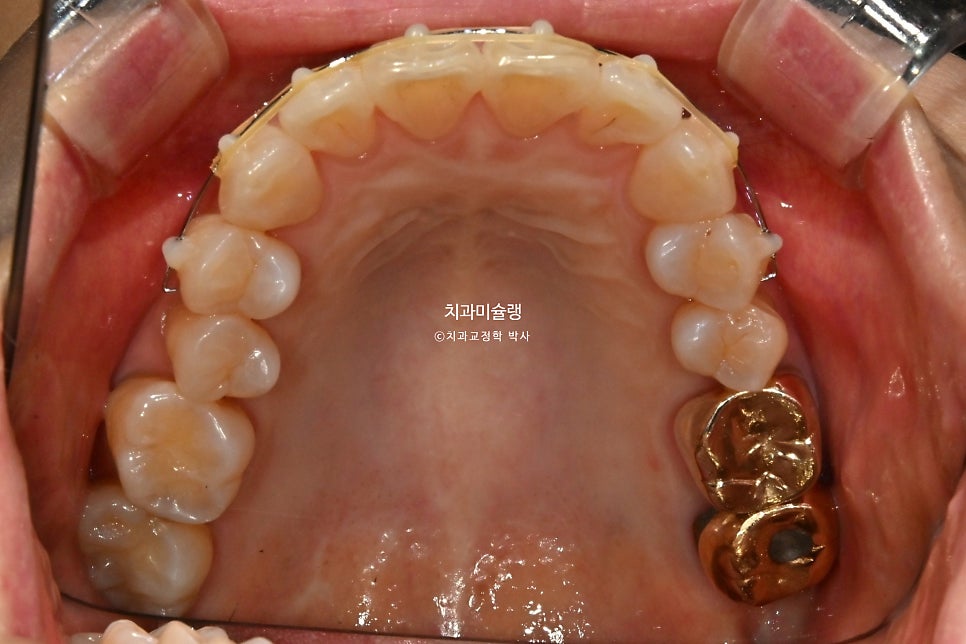

아래는 첫번째 작은어금니까지 배열이 되고 나니 두번째 작은어금니가 안으로 쓰러진 부분이 더 눈에 띄게되었습니다.

그래서 해당부분만 장치를 더 연장하는것으로 환자분을 설득했습니다.

4개월 후 경과

작은어금니까지 배열이 가지런해졌습니다.

어금니 교합은 우측은 1급, 좌측은 2급 교합 관계를 보이나, 물샐틈 없이 잘 물립니다.

고정식 유지장치까지 들어간 모습입니다.